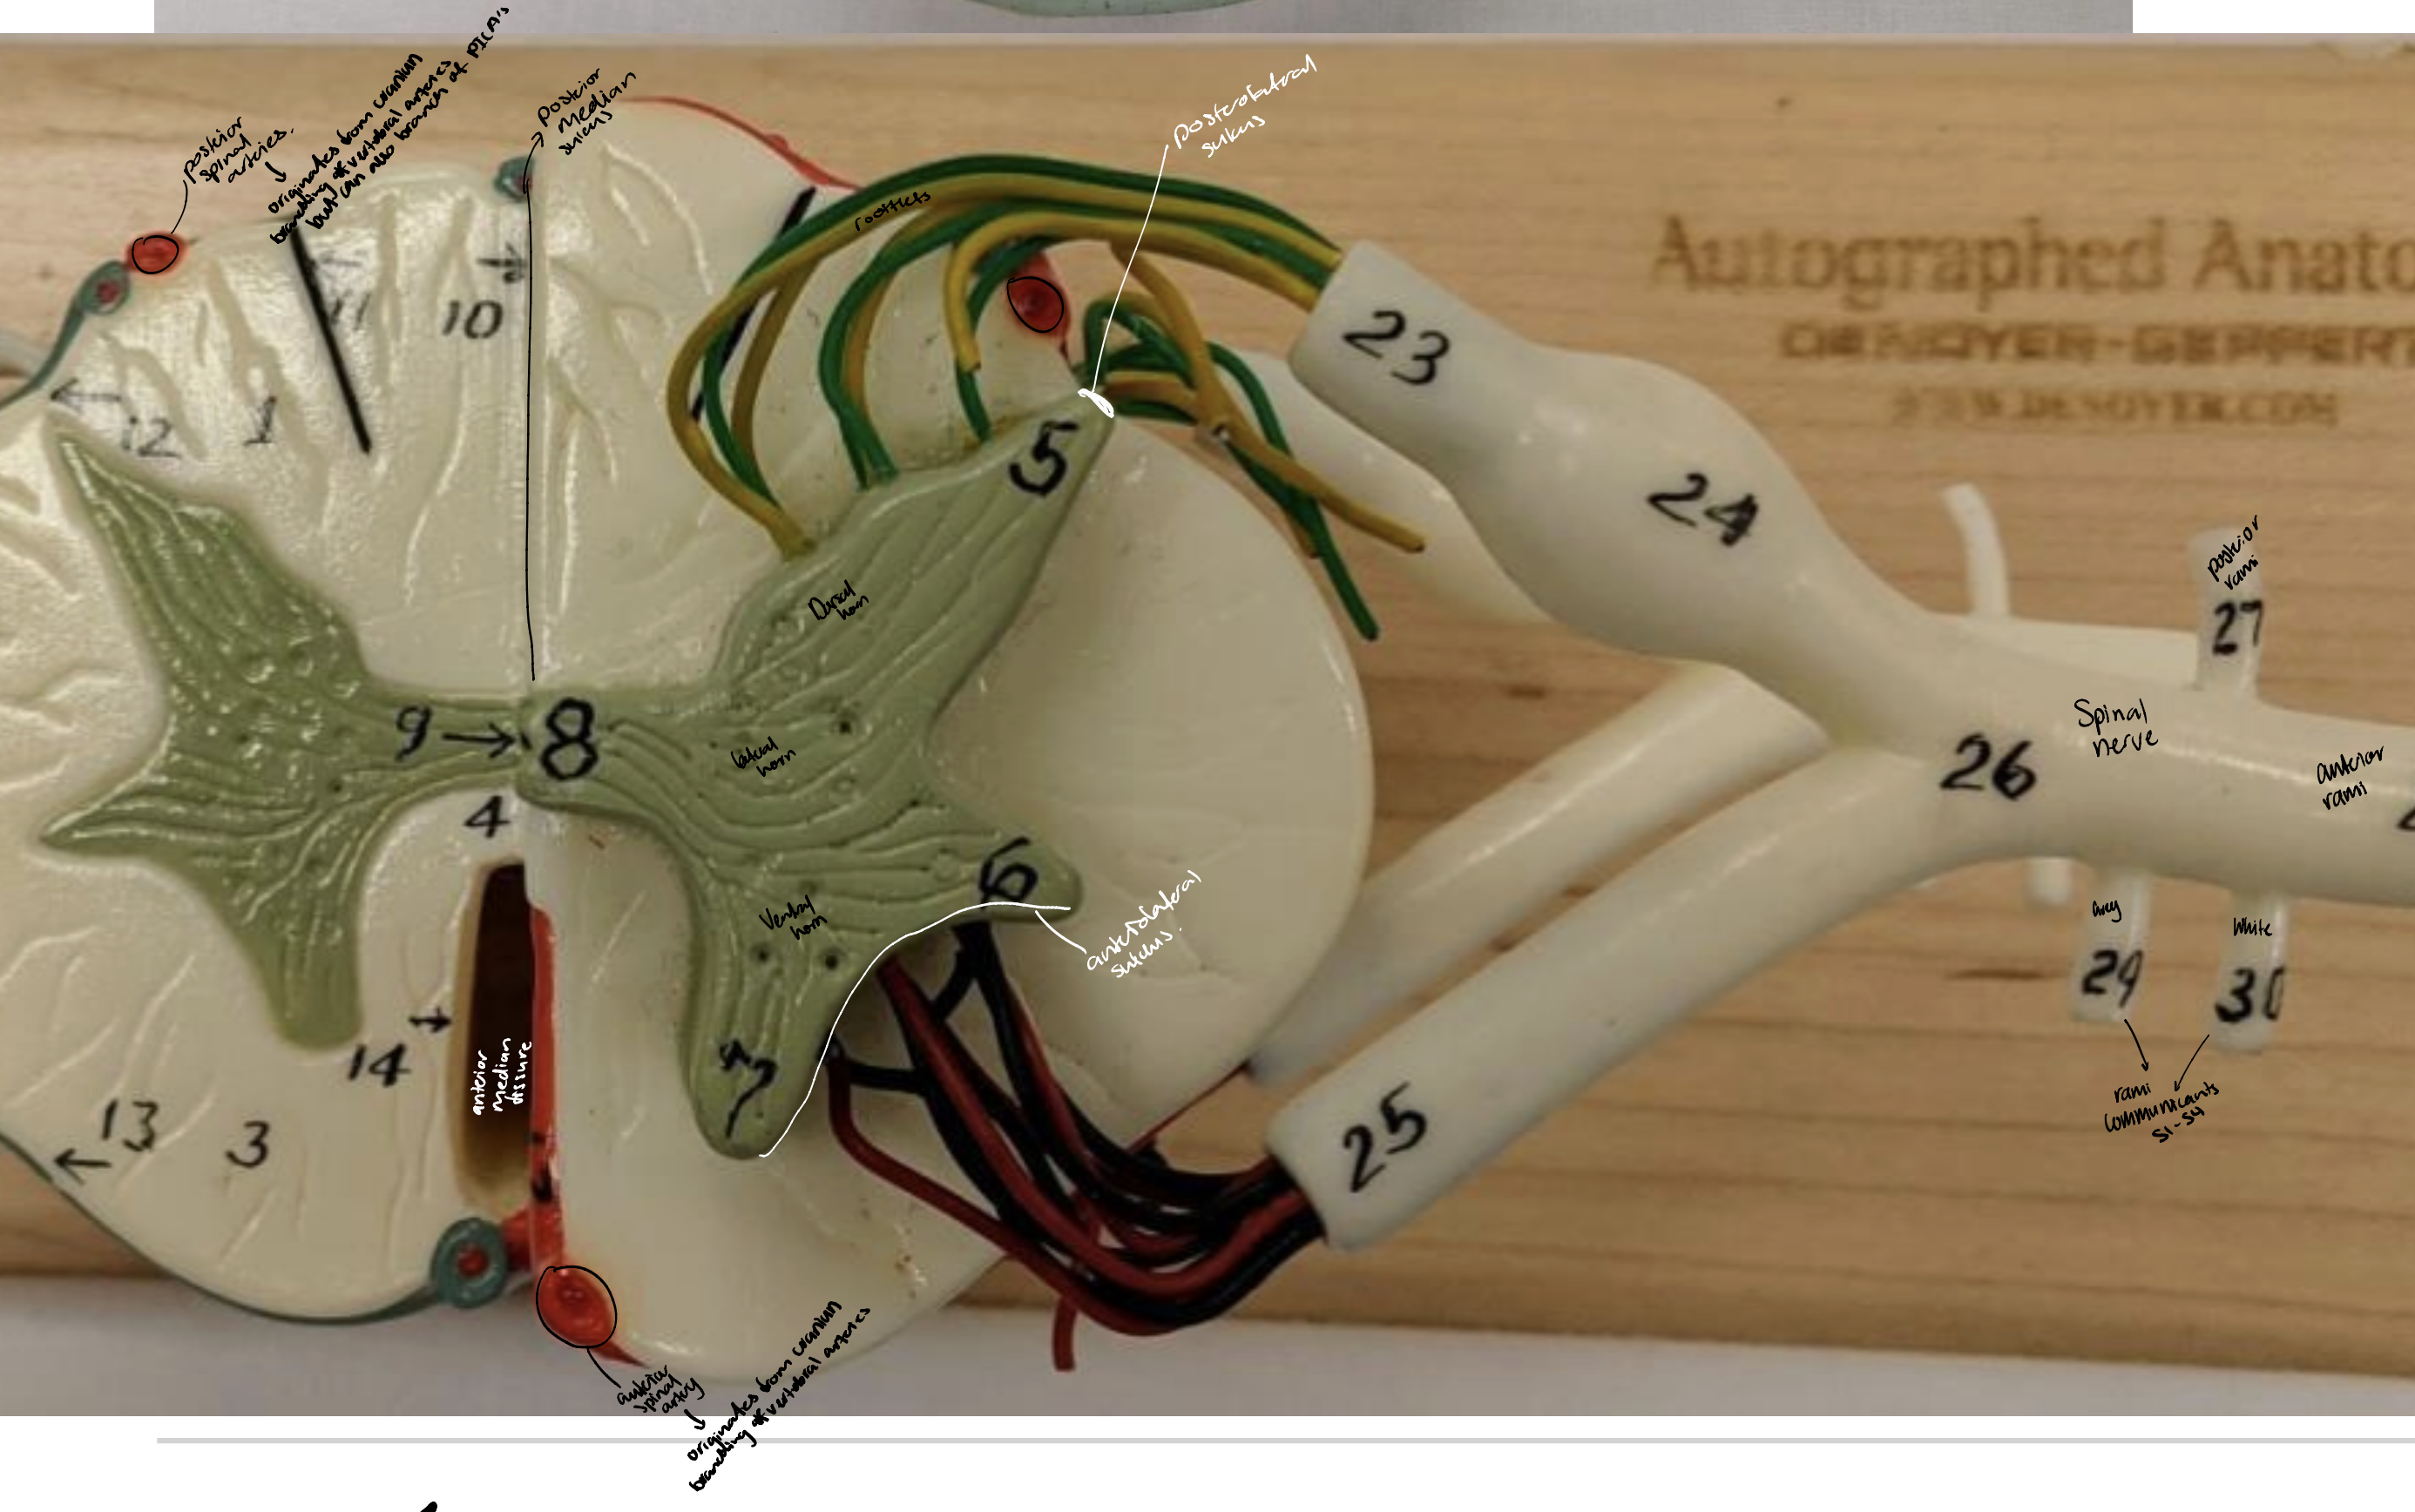

Anterior median fissure

Posterior median sulcus

Posterolateral

Anterolateral sulci

Ventral and dorsal rami

Rami communicantes

Anterior and posterior spinal arteries

The arterial supply of the spinal cord + origins

Anterior spinal artery that originates inside the cranium from branches off the vertebral arteries.

Two posterior spinal arteries that originate in the cranium as branches off the vertebral arteries or the posterior inferior cerebellar arteries, and descend along the posterolateral sulci